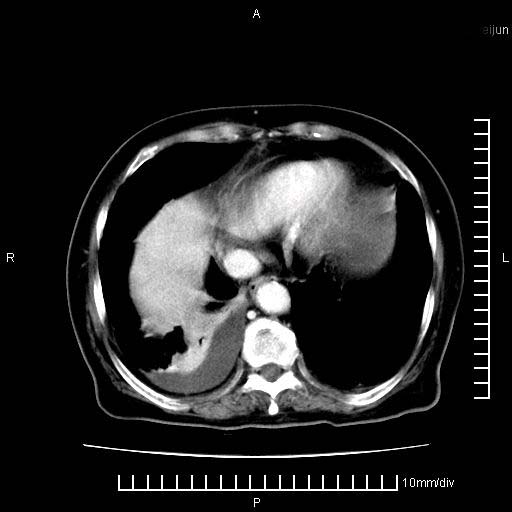

上腹疼痛月余,外院核磁诊断胰腺癌。现临床示右下腹可明显触及包块,可片子上怎么没有看到?

1.胰腺颈体部癌。

2。腹腔积液。

3。右胸腔积液,伴右肺下叶部分萎陷。

4。右肾盂囊肿。

胰腺体部癌累及周围器官,腹膜、粘连

1。胰腺ca伴腹膜腔转移

2。肝左叶低密度灶,考虑转移可能

胰腺结构模糊,胰尾部见囊性包块,周围脂肪密度增高,左肾前筋膜增厚,胸水、腹水。不符合胰腺ca伴腹膜腔转移。考虑胰腺炎伴假性囊肿形成、胸腹腔积液。

1、考虑胰腺癌伴腹膜腔转移,胸腹水。

2、肝脏转移可能。

3、右肾盂囊肿。

1)考虑胰腺癌并胰腺假性囊肿形成。2)肝内低密度灶,不排除转移。3)右肾盂积水。4)腹水。5)右侧胸腔积液并右肺下叶部分膨胀不全。

考虑胰腺ca伴腹膜腔转移、肝左叶转移、右肾积水。右胸腔积液。